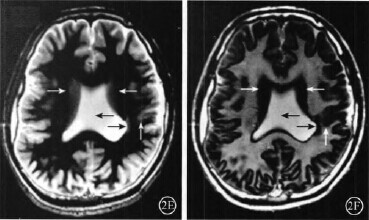

脑灰质异位,脑灰质异位图片

脑灰质异位图片

灰质异位